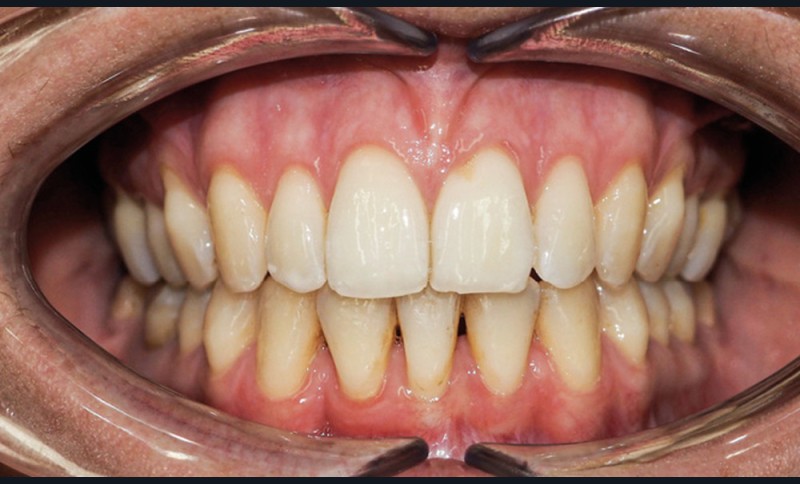

Discussion (fig. 4 à 7)

La durée du traitement a été de vingt-trois mois. Des mouvements lents ont permis un contrôle des axes incisifs mandibulaires.

Le stripping maxillaire a permis :

- de rééquilibrer les dimensions entre les incisives centrales et latérales (DDD initiale par insuffisance maxillaire) ;

- d’éviter l’apparition de triangles noirs entre les incisives [3] ;

- d’éviter la présence d’un surplomb résiduel.

Des triangles noirs sont apparus à la mandibule suite à l’extraction de 31 : ils ne sont pas exposés lors du sourire, ce qui n’entraîne pas de défaut esthétique.

La génioplastie discrète apporte un équilibre facial et une fermeture labiale non forcée, ce qui limite le risque de récidive liée à la pression musculaire.

La superposition des structures anatomiques nous montre une ingression de l’incisive mandibulaire et un maintien de l’axe ainsi qu’une distalisation en gression de l’incisive maxillaire.